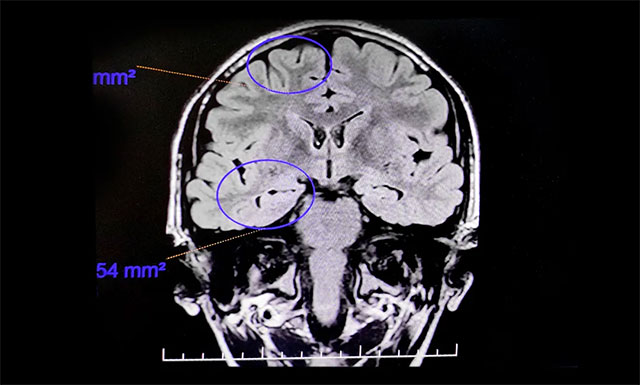

童童入院后,接受了一系列檢查,行24小時(shí)長程腦電圖監(jiān)測,提示異常腦電圖。PET/MR提示:患者右側(cè)顳前葉內(nèi)側(cè)及杏仁體、海馬區(qū)代謝較左側(cè)減低,右側(cè)海馬略萎縮,考慮致癲灶可能。

▲ 通過系列檢查評估,最終明確患者致癲灶

綜合患者病史和各項(xiàng)檢查報(bào)告,楊忠旭教授指出,患者癲癇診斷明確,經(jīng)系統(tǒng)藥物治療無任何改善,確診為難治性癲癇,應(yīng)用現(xiàn)代神經(jīng)影像學(xué)技術(shù)和電生理監(jiān)測技術(shù),能明確引起癲癇發(fā)作的“責(zé)任病變”,手術(shù)指征明顯,未見明顯手術(shù)禁忌癥。近期,在征得家屬同意后,楊忠旭教授在崔麗華主任腦電監(jiān)測輔助下為患者進(jìn)行了癲癇病灶切除手術(shù)。切除患者相關(guān)病變區(qū)域后,再次腦電監(jiān)測顯示腦區(qū)無異常放電,手術(shù)成功。